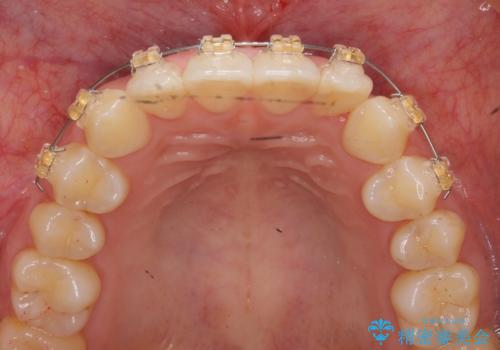

ワイヤー部分矯正治療を併用したマウスピース矯正治療

- 前歯のねじれ、深い噛み合わせ(ディープバイト)の改善を求めて来院されました。

マウスピースでは改善の難しい、歯のねじれ・ディープバイトを部分ワイヤー矯正で改善したのち、マウスピース矯正で全体の歯並びを整えていきます。

部分ワイヤー矯正を行ったことで前歯をしっかりと綺麗な歯並びへと導くことができました。